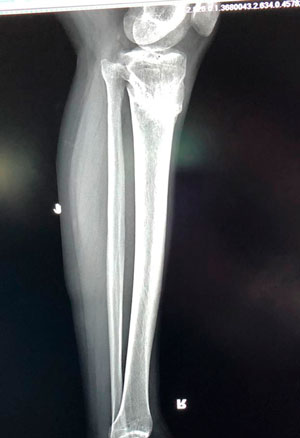

Дата операции - 12.07.2019г.

Дата снятия аппаратов - 17.10.2019г.

Срок сращения - 95 дней.